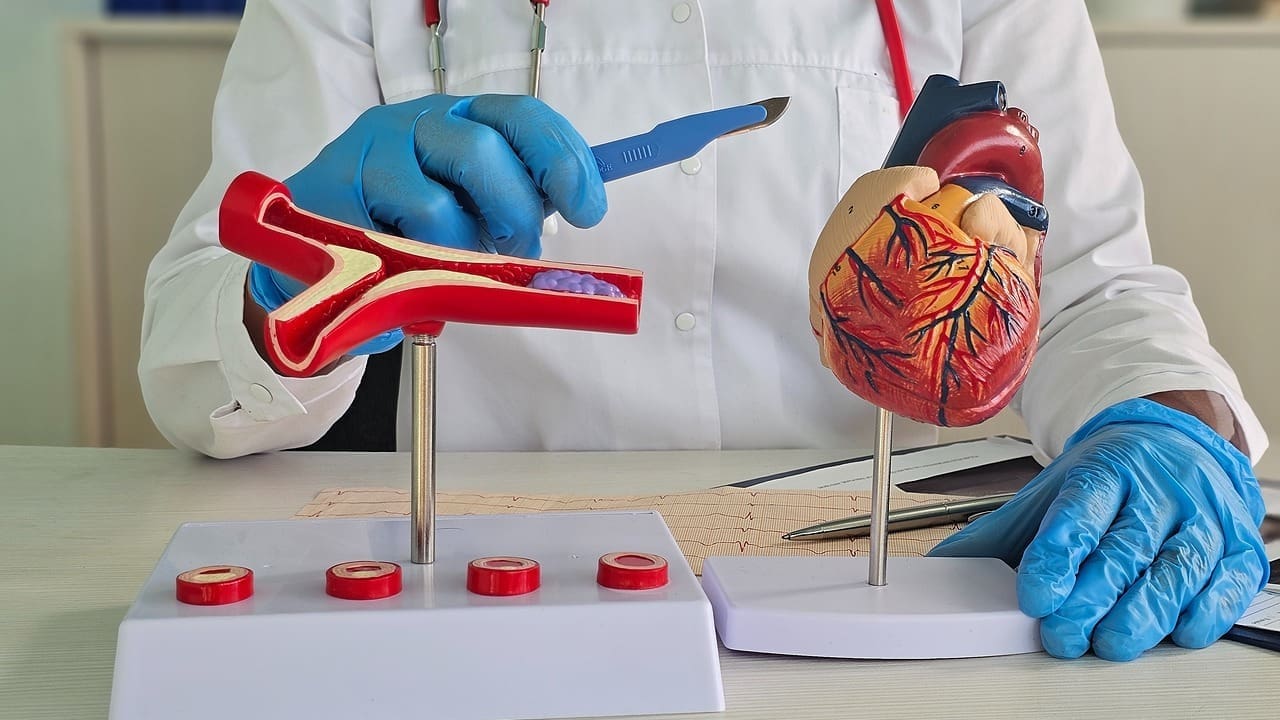

Understanding Artery Charts and Diagrams

Artery charts and diagrams are key in medical education and diagnosis. They help us see the complex network of arteries in our bodies.

These tools are vital for doctors and students. They make the arterial system’s structure and function clear. This helps in diagnosing and treating vascular conditions.

Key Benefits of Artery Charts and Diagrams

- Enhanced understanding of arterial anatomy

- Improved diagnosis of vascular conditions

- Better patient education and communication

Artery charts and diagrams show the arterial system’s details. For example, they can show the aorta’s path and its branches. This helps us see how blood is distributed throughout the body.

The table below compares different artery charts and diagrams. It shows their features and uses.

| Type of Diagram | Description | Use |

| Arterial System Overview | Illustrates the overall structure of the arterial system | Medical education, patient education |

| Detailed Artery Chart | Provides detailed information on specific arteries and their branches | Diagnosis, treatment planning |

| Simplified Diagram | Simplifies complex arterial structures for easier understanding | Patient education, basic medical training |

It’s important to understand artery charts and diagrams for medical practice or education. These tools improve understanding and communication in healthcare.